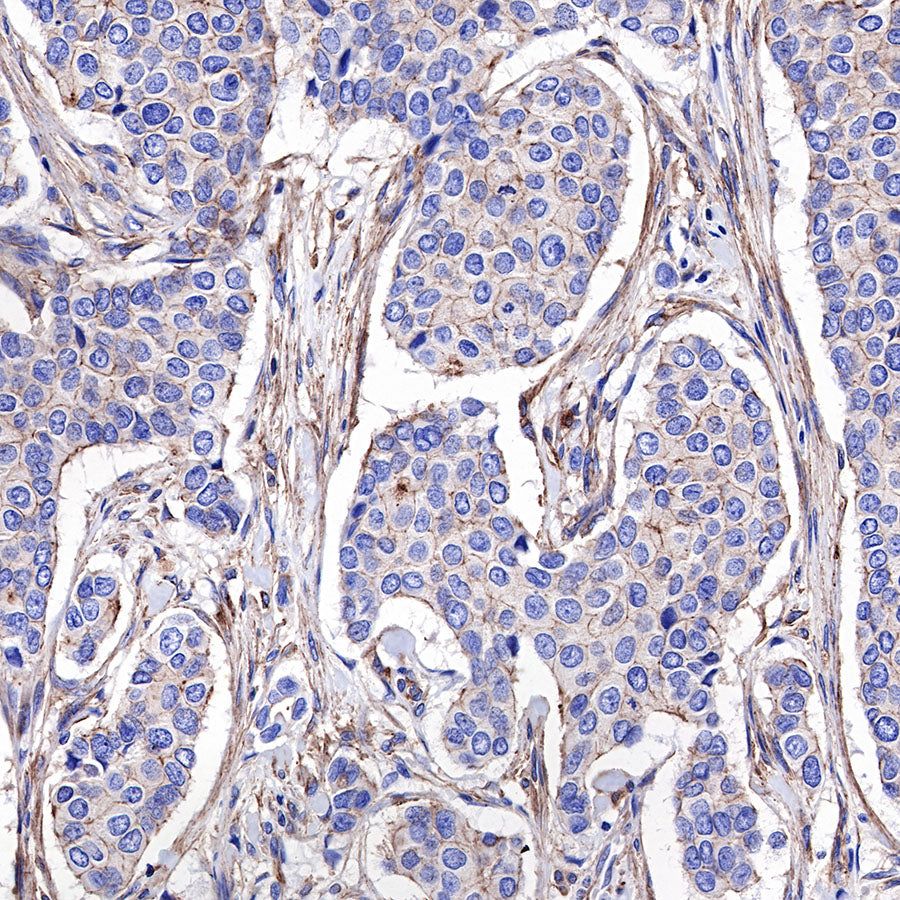

IHC shows positive staining in paraffin-embedded human breast cancer. Anti-α-Actinin-1 antibody was used at 1/2000 dilution, followed by a HRP Polymer for Mouse & Rabbit IgG (ready to use). Counterstained with hematoxylin. Heat mediated antigen retrieval with Tris/EDTA buffer pH9.0 was performed before commencing with IHC staining protocol.